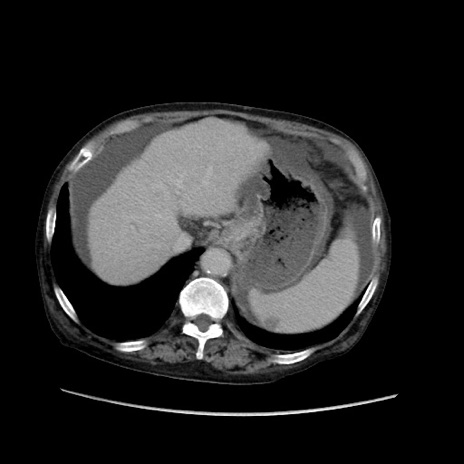

症例31(横断像)

【症例】80歳代 女性

【主訴】腹部膨満感

【現病歴】他院にて肝硬変にてフォロー中。1週間前から便秘、腹部膨満感、臍部腫瘤あり受診となる。

【既往歴】肝硬変

【身体所見】腹部膨隆あり、皮膚変化なし、疼痛なし。

【データ】WBC 4600、CRP 0.25